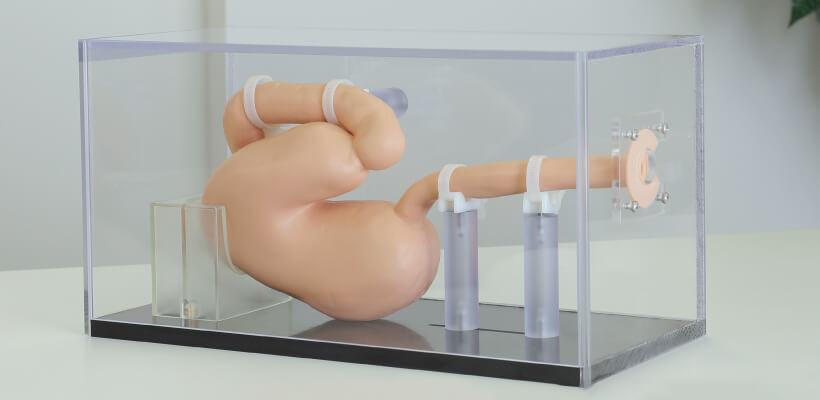

JMC's commitment to the digestive system model